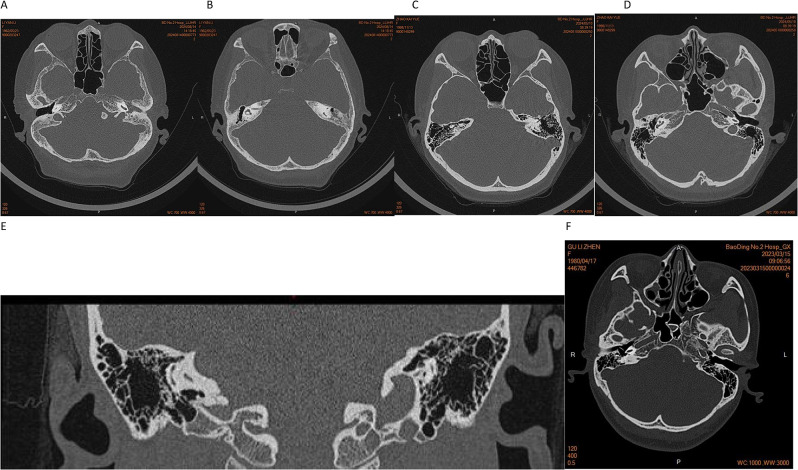

Objective: Exploring the temporal bone Computed Tomography (CT) features and clinical characteristics of patients with ethmoid sinus lesions (ESL) combined with high jugular bulb (HJB) and pulsatile tinnitus symptoms.